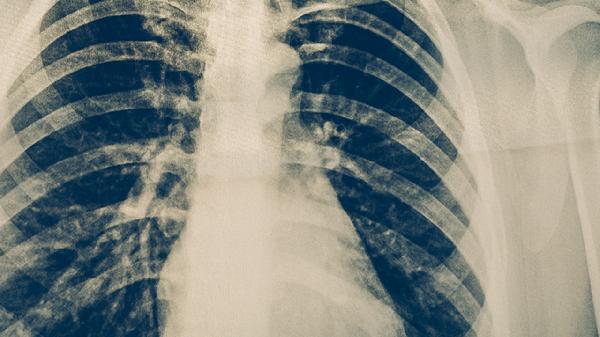

治疗期间须严格遵医嘱完成全疗程用药,避免漏服导致耐药性升级。保持高蛋白饮食和适度运动有助于改善营养状态,隔离期需佩戴口罩防止传播。建议每3个月复查胸部CT评估病灶吸收情况,治愈后仍需随访2年监测复发。出现咯血、持续发热等症状应及时复诊调整方案。